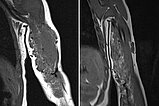

Zur weiteren Sicherung der Differentialdiagnose wird bei dem Kind auch eine MRT durchgeführt. Hier abgebildet eine koronare, T2-gewichtete, fettunterdrückte STIR-Sequenz. Der Tumor ist hier stark hyperintens (weiß im Bild) und scharf zum umgebenden Gewebe abgegrenzt. Er durchdringt alle Gewebeebenen und enthält zentral als Zeichen einer starken arteriellen Perfusion signalfreie Areale, sogenannte Flow-voids.

Vergleich der koronaren, T1-gewichteten MRT vom Februar 2019 (linkes Bild) zu September 2021 (rechtes Bild). In dieser T1-Wichtung wird Fett hyperintens (weiß) dargestellt. Im rechten Bild ist gut zu sehen, dass die Fettanteile im Tumor im Laufe der Zeit zugenommen haben. Dies ist typisch für ein teilweise in Involution befindliches infantiles Hämangiom (mehr Fettanteile, weniger Gefäßproliferate).